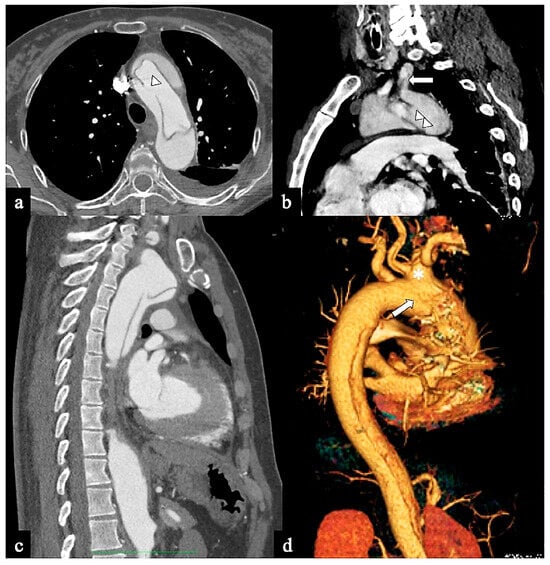

- Configuration 1 (or DTA entry): Among the cohort, 25 out of 36 patients (69.5%) presented with a type B AD or descending-entry type, with the primary entry tear distal to the left subclavian artery (zone 3). The extension of the flap occurred antegradely into the descending aorta, with or without the involvement of the abdominal aorta, and retrogradely into the aorta until the brachiocephalic trunk (BCT) (Figure 3). We describe this configuration as non-A non-B dissection with a retrograde pathway of dissection, as the entry site of the flap is in the descending aorta with retrograde arch involvement. According to Stanford classification, this configuration was present in 14% of type B AD patients. Previous studies have documented DTA entry type to be present between 10% and 25% of patients with acute type B dissection, sometimes as an intramural hematoma [33,34,35]. Patients presenting with DTA entry non-A non-B dissection demonstrated a prevalent origin of BCT and LCCA in 20% and an arch origin of the left vertebral artery in 4%. Among these cases, the distal extent of dissections was observed in various locations: the thoracic aorta in 9 patients, the abdominal aorta in 7 patients, and the pelvic circulation in 9 patients. Involvement of specific arteries was noted, including the left subclavian (n = 5), left common carotid (n = 1), or innominate (n = 1) arteries. Six of these DTA entry patients, who were initially managed with medical therapy, necessitated hybrid or surgical aortic repair within 10 days after the onset of dissection due to persistent pain (3/5), new organ malperfusion (2/5), or rapid aortic growth (1/5). Forty percent of these patients underwent treatment with optimal medical therapy and close imaging surveillance, while 60% received hybrid or open surgical therapy.